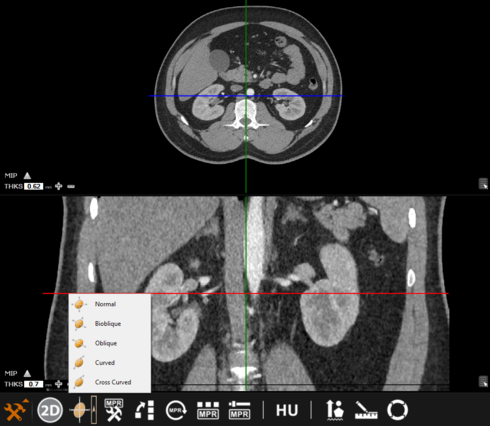

MPR tools

There are six icons available in MPR mode, an overview is given below:

MPR mode – there are five different modes to choose from (normal, bioblique, oblique, curved, and cross-curved).

MPR settings – this enables the user to see reference view (only available on normal and oblique modes); or to see panoramic view (only available for curved mode)

Generate MPR series – generates a new series using normal or oblique modes.

MPR reset – resets any action performed while in MPR mode.

Select MPR protocol – adjusts the viewing (hanging) protocol within the MPR viewer.

MPR fusion properties – enables fusion between two modality types (CT-PET or MR-PET)